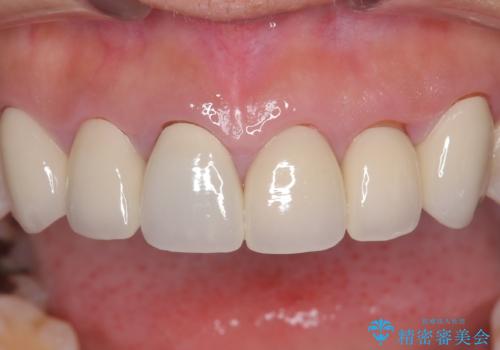

前歯の破折も1日で解決!抜歯即時インプラントで自然な笑顔へ

今回の治療では、まず原因となっていた前歯を慎重に抜歯し、その直後にインプラントを埋入しました。抜歯即時埋入は、歯を失うのとほぼ同時に新しい歯の土台を確保できるため、骨の吸収を防ぎ、仕上がりの美しさを保つ上で非常に有効です。また、治療当日に仮歯を装着することで、歯がない期間をなくし、患者様の精神的なご負担にも配慮しました。最終的に、周囲の歯と調和したオーダーメイドのセラミッククラウンを装着。機能性だけでなく、天然歯と見分けがつかないほどの自然で美しい前歯を取り戻していただけました。